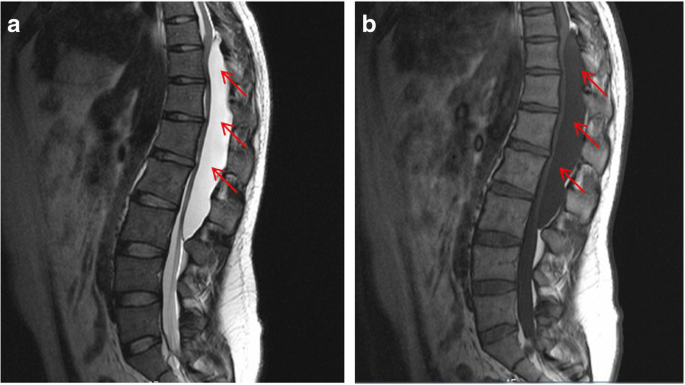

This is a 26-year-old man who experienced right lower limb weakness for 2 years and the weakness exacerbated in last half year. He visited the second affiliate hospital of the Zhejiang University School of Medicine. A physical examination indicated the result of the straight leg raising test was positive and also muscle atrophy. The muscle power of the right lower limb had decreased to grade 3. There was no sensory impairment. Magnetic resonance imaging revealed an intraspinal extradural tumor over T10 to L3 (Fig. 1). It appeared to be a spinal extradural arachnoid cyst (SEAC). To confirm whether the fistula existed between the subarachnoid space and arachnoid cyst, and to localize the position of the fistula, we performed a real-time technique. First, we injected contrast medium into the cyst under fluoroscopy. After 1 h the follow-up computed tomography (CT) was administered, and it revealed there was no contrast-infiltration into the subarachnoid space (Fig. 2). We then extracted about 20 mL of fluid from the cyst. The follow-up magnetic resonance imaging on the same day indicated the cyst did not become smaller (Fig. 3). A “one-way valve” fistula was suspected such that cerebral spinal fluid could pass into the cystic space from the subarachnoid space but could not flow in the opposite manner. Therefore we designed a procedure to localize the fistula. We penetrated two needles into the cyst and subarachnoid space separately in the L3/L4 level under digital subtraction angiography (Fig. 4). Pending the fluid drained through those two needles, we injected 10 mL of contrast medium slowly into the subarachnoid space and a little contrast medium infiltrated into the cystic space horizontally at the T12/L1 level. We then administered high resolution computed tomography (HRCT) immediately to confirm the position in the axial plane. The HRCT revealed a funnel-shaped enhancement between the lower edges of the T12 body and the left nerve root, and this is the accurate position of the fistula (Fig. 5).